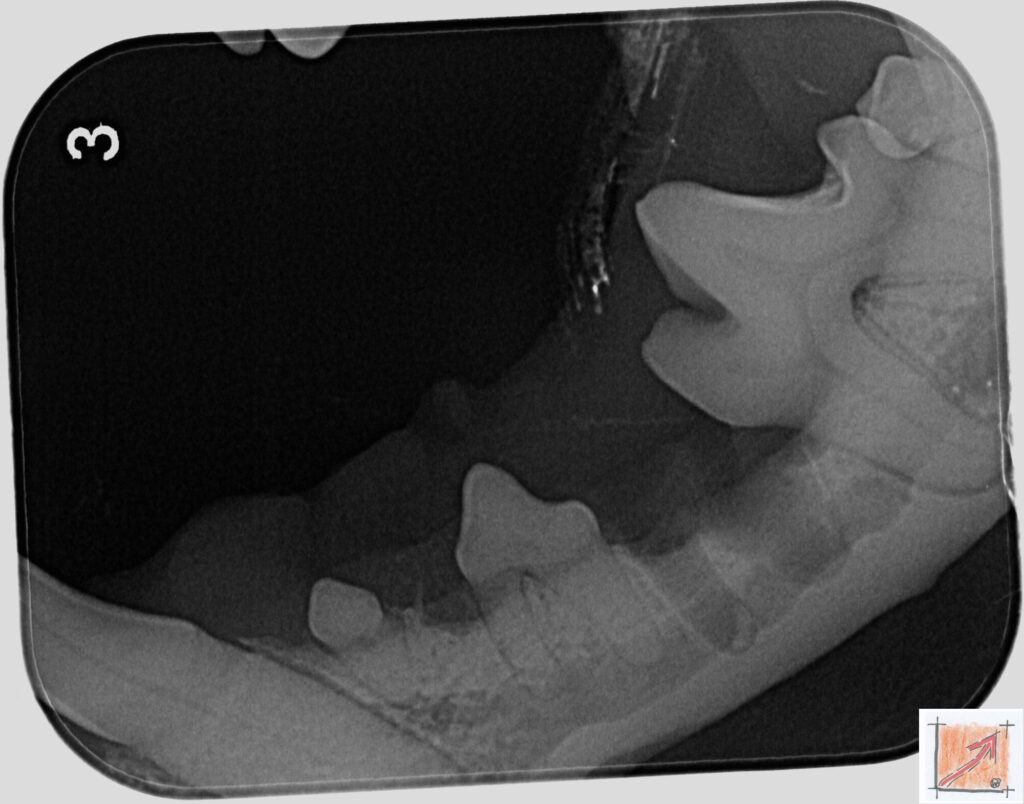

Röntgenbilder vom Thierrischen Orakel bei der Zahn-OP:

Warum Dentalröntgen beim Chihuahua lebenswichtig ist:

Ein Blick hinter die Kulissen von Chihuahua-Zähnen:

In dieser Galerie zeigen wir exklusive intraorale Röntgenaufnahmen einer Zahn-Operation beim Thierrischen Orakel als Chihuahua vom BauFachForum. Während oberflächlicher Zahnstein oft sichtbar ist, verbirgt sich die wahre Gefahr für das Herz meist unter dem Zahnfleischsaum.

Das digitale Dentalröntgen ist der Goldstandard in der modernen Tiermedizin, um parodontale Entzündungsherde und Wurzelabszesse sicher zu diagnostizieren. Für Chihuahuas wie dem Thierrischen Orakel, mit Mitralklappeninsuffizienz ist dieser diagnostische Schritt essenziell. Nur wenn versteckte Bakterienherde an der Zahnwurzel oder mit dem Fachbegriff Apikalabszesse erkannt und saniert werden, kann das Risiko einer bakteriellen Endokarditis oder einfach ausgedrückt einer Herzinnenhautentzündung minimiert werden.

Unsere Aufnahmen von Patienten dem Thierrischen Orakel verdeutlichen den Unterschied zwischen einer rein optischen Zahnreinigung und einer medizinisch fundierten Sanierung unter Röntgenkontrolle.

Chihuahua Mitralklappeninsuffizienz Trachealkollaps:

Wichtig ist im Vorfeld die Zahnhygiene des Chihuahuas. Die Bilder zeigen Dentale Röntgenbilder vom Thierrischen Orakel als Chihuahua-Hund während seiner Zahn-OP. Darstellung von Kieferknochen und Zahnwurzeln zur Diagnose von Parodontitis.

Zahnröntgenaufnahme bei Chihuahua Thierry:

Untersuchung der Zahnwurzeln auf Entzündungsherde als Prophylaxe gegen bakterielle Endokarditis.

Intraorales Dentalröntgen eines Chihuahuas:

Die Bilder zeigen Zähne und Wurzelstrukturen im Unterkiefer zur Planung einer Extraktion bei hochgradigem Zahnstein.